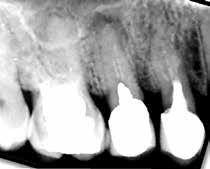

Fig. 11. A. Skematisk illustration af tand med pulpasten i pulpakammer og rodkanaler, hvilket kan gøre det vanskeligt at lokalisere kanalindgangene og udrense kanalerne (18). B. Bitewing-optagelse viser generaliseret dannelse af pulpasten i molarerne (pile). C. Periapikal optagelse af -6 med omfattende forkalkninger i pulpakammer og rodkanaler (pil).

Fig. 11. A. Schematic illustration showing tooth with pulp stone in the chamber and root canals creating potential difficulty in locating root canal orifices and instrumentation (18). B. Bitewing radiograph showing generalized pulp stone formation on molars (arrows). C. Periapical radiograph of mandibular left first molar with extensive calcifications in the pulp chamber and root canals (arrow).